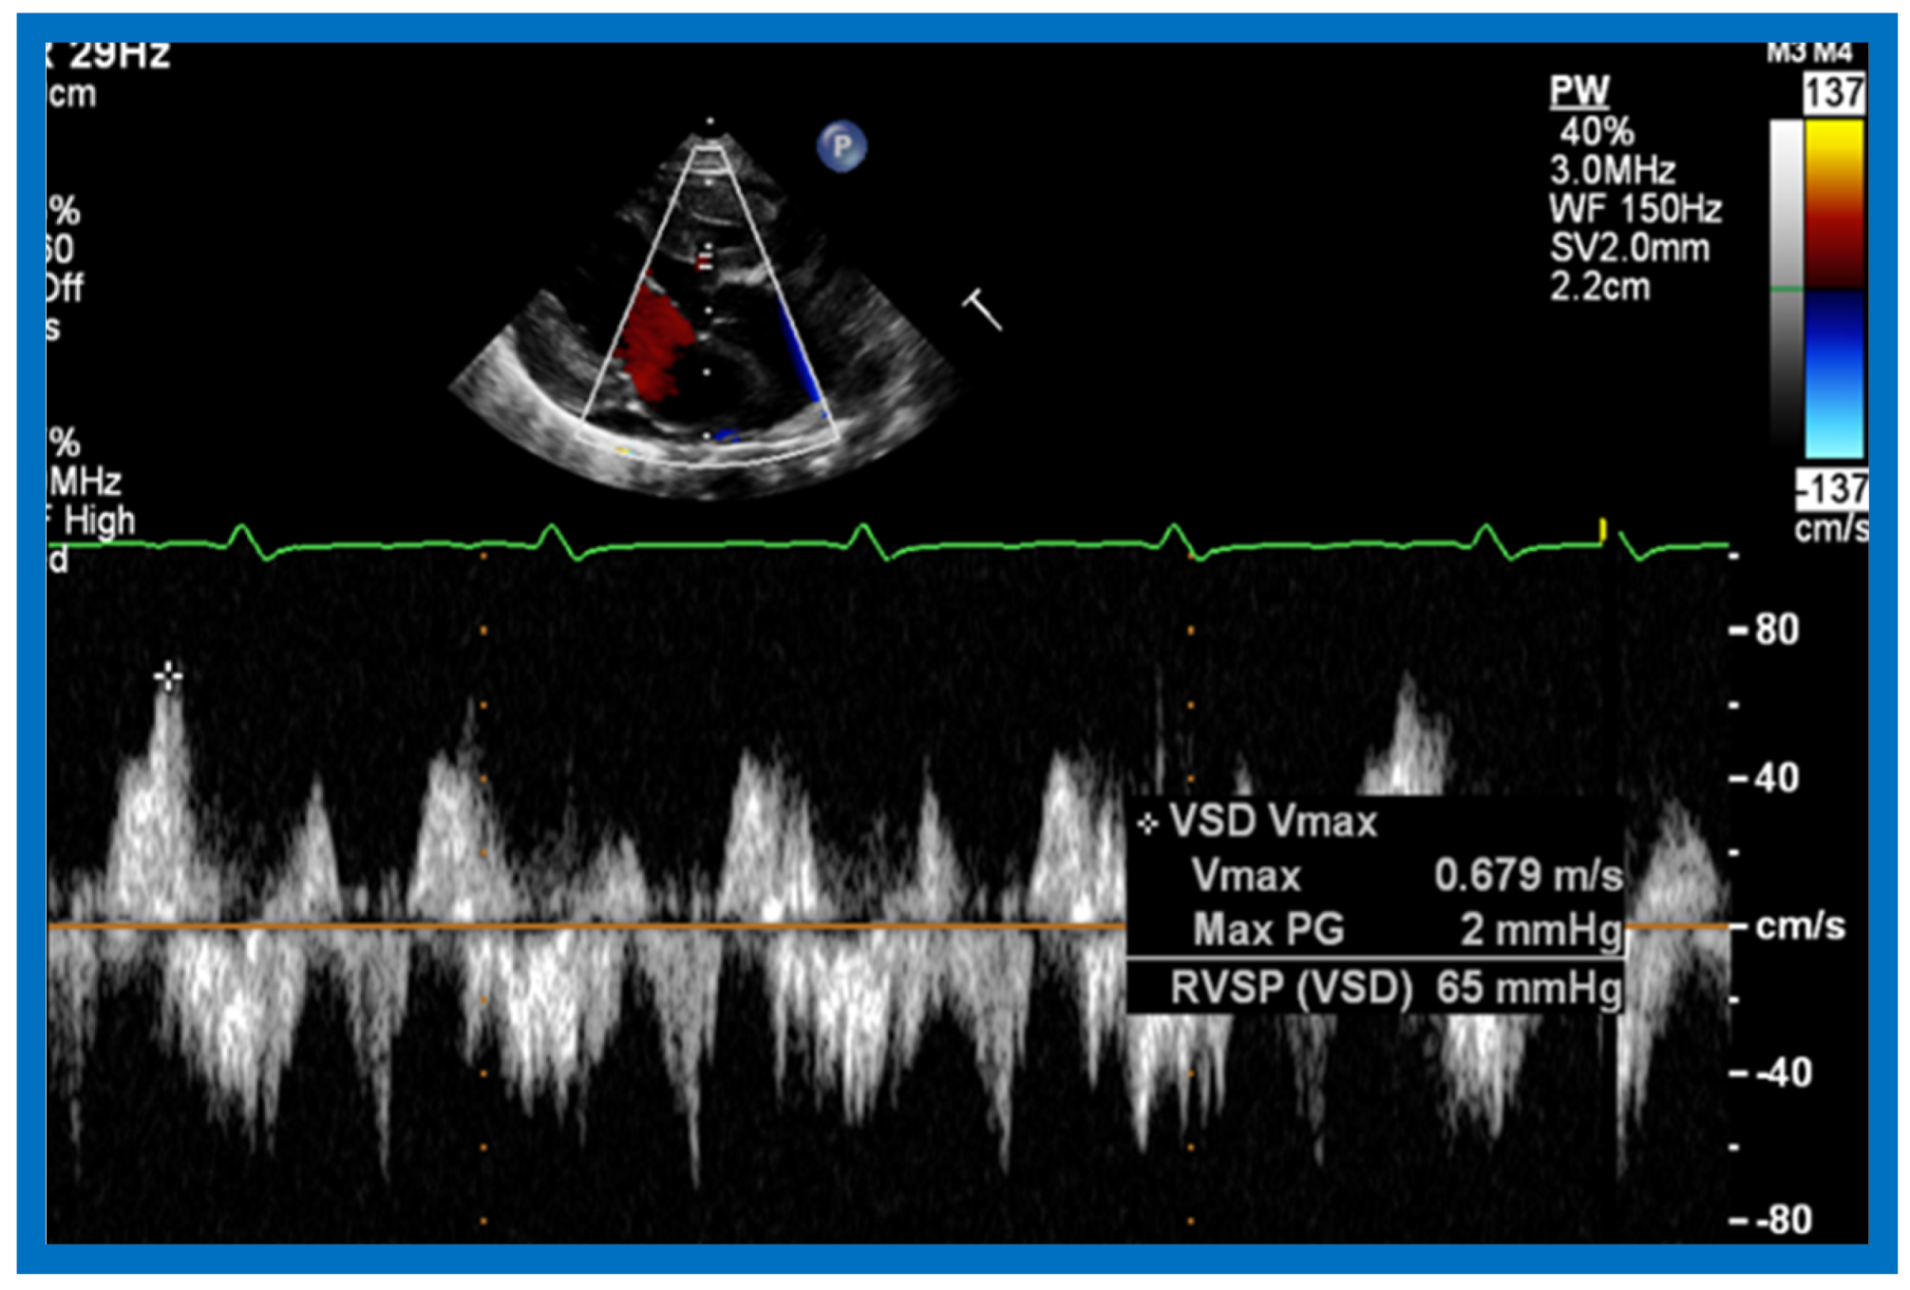

Then, the ventricular septum is evaluated; the ventricular septum is intact in most Type Ia cases. In children with Type I (normally related great arteries), the VSD supplies pulmonary blood flow (Figure 20) while in patients with Type II (transposition the great arteries), the VSD allows blood to flow into the systemic circuit (Figure 21 and Figure 22). In Type I patients, the VSD is demonstrated by 2D (Figure 20A) and the left to-right shunt across it by color (Figure 20B), pulsed and CW (Figure 20C) Doppler signals. Interrogation of the right ventricular outflow tract and pulmonary artery region is performed; peak Doppler flow velocity across the right ventricular outflow tract and pulmonary valve is helpful in identifying obstruction across these sites. The Doppler data from the VSD and RVOT are also helpful in estimating of pulmonary artery pressures. In these Type I babies, the 2D size of the VSD and the peak Doppler flow velocity across it are useful in quantifying the size of the VSD (Figure 20); the higher the VSD Doppler velocity, the smaller the defect. However, in patients with pulmonary hypertension, severe infundibular or valvar pulmonary stenosis, the VSD Doppler velocities do not reflect the size of the VSD. Barring these exceptions, right ventricular and pulmonary arterial pressure may be estimated using modified Bernoulli equation (RV/PA systolic pressure = systolic BP − 4V2).

In Type II patients, the VSD may be small, causing obstruction to blood flow to the systemic circuit; therefore, the size of the VSD should be ascertained by 2D (Figure 21 and Figure 22), color Doppler (Figure 22), pulsed (Figure 25) and CW Doppler, as necessary. In these Type II patients, the high VSD velocity is indicative of subaortic obstruction. Interrogation of left ventricular outflow and PA region may reveal pulmonary or subpulmonary stenosis; the higher the velocity, the more severe the obstruction. Study from suprasternal notch may show aortic coarctation (Figure 26), which is not uncommon in patients with the Type II anatomy.

Figure 25.

Selected video frame of continuous wave Doppler across the ventricular septal defect of the same baby shown in Figure 22. Low velocity flow across the ventricular septal defect suggests that the defect is nonobstructive. Reproduced from Rao P.S. [39].